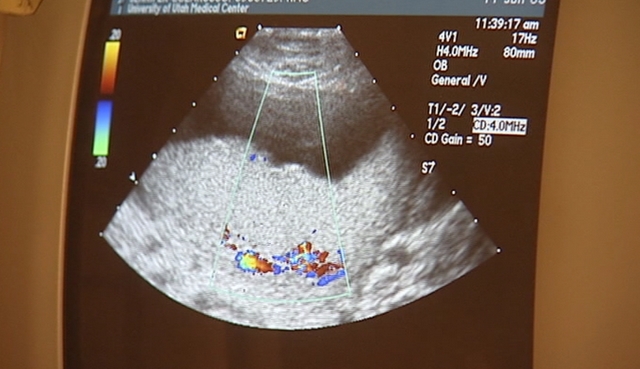

SALT LAKE CITY — Fetal heart rates are monitored to indicate a baby's overall health. But according to a new study by doctors with Intermountain Healthcare, the heart rates are too often considered indeterminate and therefore shouldn't be used to make decisions regarding emergency cesarean deliveries.

Maternal-fetal medicine specialists believe fetal heart rate patterns may not be a good indicator of a baby's health, and may lead to such unnecessary interventions and higher health care costs.

Heart rate patterns were monitored using a three-tiered classification system, developed in 2008 by the Eunice Kennedy Shriver National Institute of Child Health and Human Development. However, the study states that the system has been in need of an update because reliance on the various classifications has tempted more doctors to take possibly unnecessary precautions, including an increasing number of C-section and forceps deliveries.

While the majority of the 48,444 babies born at 10 Intermountain hospitals during a 28-month study period showed normal heart rate patterns throughout delivery, some of those, about 39 percent, changed during the final two hours of delivery. Those babies then fell into a mid- range clinical definition, making their heart rate pattern significance uncertain, and health factors basically "indeterminate."

Abnormal or rare heart rate patterns, which typically indicate a problem, were noticed in only 0.1 percent of the patients studied, and resulted in admission to the neonatal intensive care unit about half the time.

According to study results, the vast majority of babies born under the "indeterminate" category had no short-term problems after delivery and only 0.2 percent of them required admission to the NICU, which means that using those uncertain patterns as an indicator of fetal health is an unreliable method, researchers say.